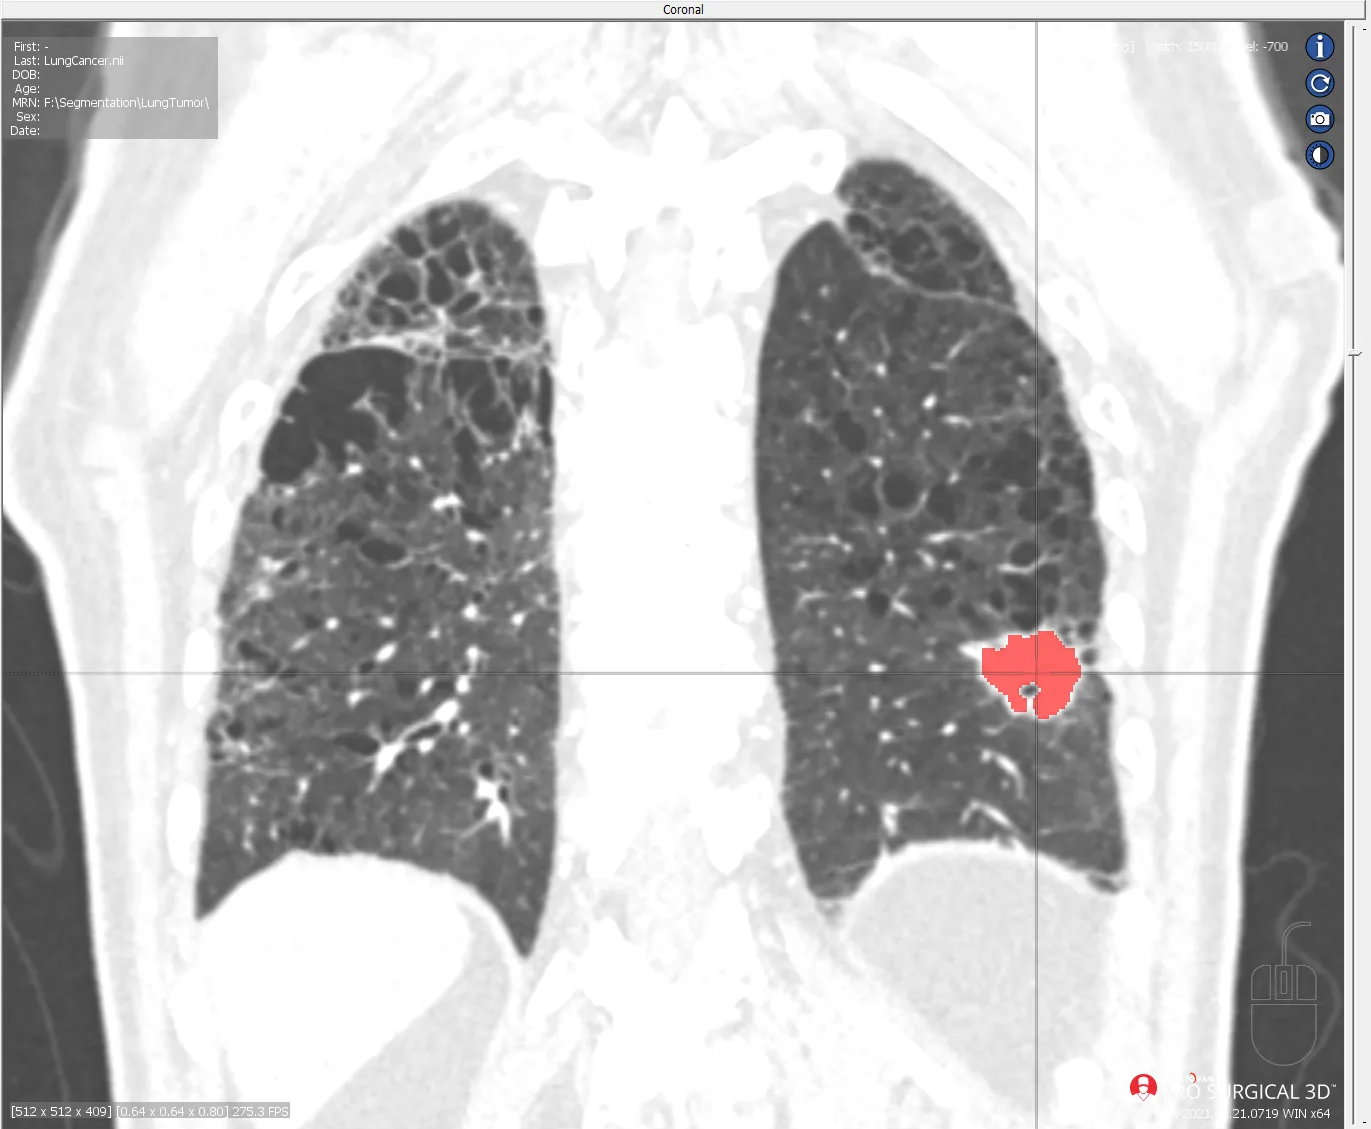

Imagine a CT scan of a lung afflicted by cancer. Amidst the labyrinth of tissues, identifying the precise location and extent of the malignancy is akin to finding a needle in a haystack. This is where segmentation software shines. With Segmentation for Pro Surgical 3D, the intricate task of delineating anomalies becomes remarkably straightforward. The software's intuitive interface empowers medical professionals to swiftly and accurately segment structures of interest, such as tumors, with unparalleled ease. Through advanced user-friendly tools, intricate details are cleanly and clearly identified, enabling clinicians to formulate targeted treatment plans with confidence. Additionally, each segmentation of cancerous growths or anomalous conditions builds upon previous datasets. This iterative cataloging of various patients with different ailments, over time, builds the dataset necessary to train Machine Learning (ML) and Artificial Intelligence (AI) based algorithms to aid in the early and consistent detection of threats to patients. In the CT scan of a set of lungs below, the cancerous mass stands out prominently, meticulously delineated by Segmentation for Pro Surgical 3D. This visual representation not only aids in diagnosis but also serves as a roadmap for surgical intervention, ensuring precise and effective treatment strategies.

CT Lung Cancer